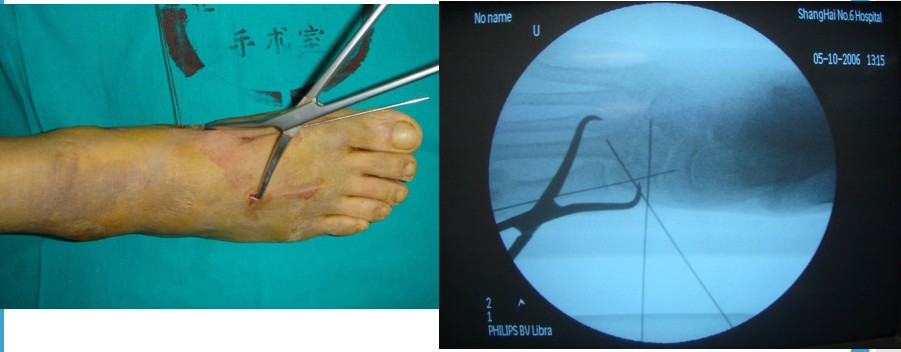

手术治疗Lisfranc损伤有两个手术时间窗,即伤后6-8h和伤后7天后。

如果不能在伤后6-8小时手术,应耐心等待,待患足肿胀消退出现褶皱时再行手术治疗。若冒然进行手术,可能会加重术后肿胀,或者皮肤不愈合以及皮瓣因压力过大而坏死。

切开复位内固定急诊手术指征:开放性骨折;血管神经损伤(足背动脉);骨筋膜室综合症。

内固定选择1、克氏针:优点是手术简单、时间短、对周围组织损伤小,缺点是固定不坚强、复位丢失等情况时有发生。2、可吸收螺钉:优点是不需行二次手术取出内固定物,缺点是固定强度不及传统螺钉3、小螺钉系统:经典 --- 3.0mm、3.5mm、4.0mm4、空心螺钉:3.0mm、4.0mm、4.3mm 、4.5mm5、微型钢板:跨关节固定,对于严重的跖骨粉碎性骨折的患者,螺钉无法固定时,建议选择微型钢板桥接固定6、骑缝钉

手术切口选择单一切口、双切口

双切口能充分显露所有的跖跗关节;第一切口位于第一、二跖骨之间。该切口利用了两个间隙,一个拇长伸肌腱内侧,一个为拇短伸肌腱外侧。分别可显露第一跖骨、内侧楔骨和第二跖骨、中间楔骨。通过延长皮肤切口,可以直视第三跖骨和外侧楔骨。第二切口位于第四、五跖骨之间,可以显露其与骰骨之间的关节。

根据三柱理论1、首先复位内侧柱并临时固定 2、再复位固定中间柱3、如外侧柱移位可能需双切口

手术从第一跖骨和内侧楔骨开始。首先直视下复位该关节,评价楔骨之间的稳定性,关节囊通常撕裂,但仍然需要掀开以充分显露关节,清除关节内的软组织和软骨碎片。

内侧柱稳定后,开始处理第二跖骨和中间楔骨。点式复位钳由第二跖骨基底部外侧远端斜向内侧楔骨内侧面的近端夹持,注意避免第二跖骨向下移位,发生复位不良。

若楔间关节仍不稳,可使用楔骨间螺钉;固定内侧两跖骨后,通常第三跖骨已经足够稳定,若仍未复位,可以参考第一跖骨固定方法固定。通过第二切口固定第4、5跖骨。可以使用克氏针固定。

Lisfranc损伤骨折复位标准:1、C形臂透视显示正、侧、斜位均为正常解剖复位2、如复位后第1、2跖骨基底间隙和内、中楔骨间隙<2mm,跖跗骨轴线<15°为近解剖复位,可以接受,超过这个范围的移位则无法接受3、复位好后,沿第一跖骨轴线向内侧楔骨逆行拧入一枚4.0mm皮质骨螺钉。螺钉由关节远侧1.5-2.0cm处进入,平行于足底或略向跖侧。